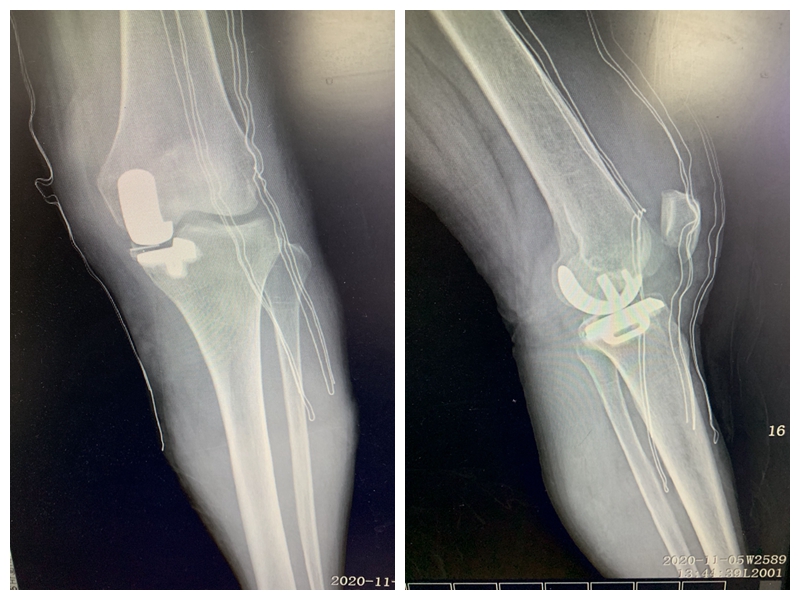

近日,我院骨科在戴福全名医工作室医务人员和麻醉科的共同努力下,完成了我市首例“左膝关节内侧单髁置换术(活动平台)”,解决了患者因膝关节退变而产生的疼痛及功能障碍。此手术的成功开展,标志着我院骨科的关节外科水平达到了新的高度。 患者因左侧膝关节内侧反复疼痛伴活动受限1年,严重影响日常生活,为求进一步治疗来我院就诊。综合评估病情后,戴福全主任医疗团队考虑为左膝关节单间室骨性关节炎,虽已丧失保守治疗机会,但行全膝关节置换术为时过早。 2020年11月2日, 确定了手术方式和术后快速康复方案后,在手术室医护人员的配合下,戴福全主任医疗团队为患者成功实施左膝关节内侧单髁置换术。

术后第三日,患者即下地站立行走,成功解决了患者左膝关节疼痛及关节功能问题。

膝关节单髁置换术仅对膝关节病变的单一间室进行表面人工关节置换术,保留了膝关节全部的韧带及其余间室关节软骨,从而实现术后快速康复。